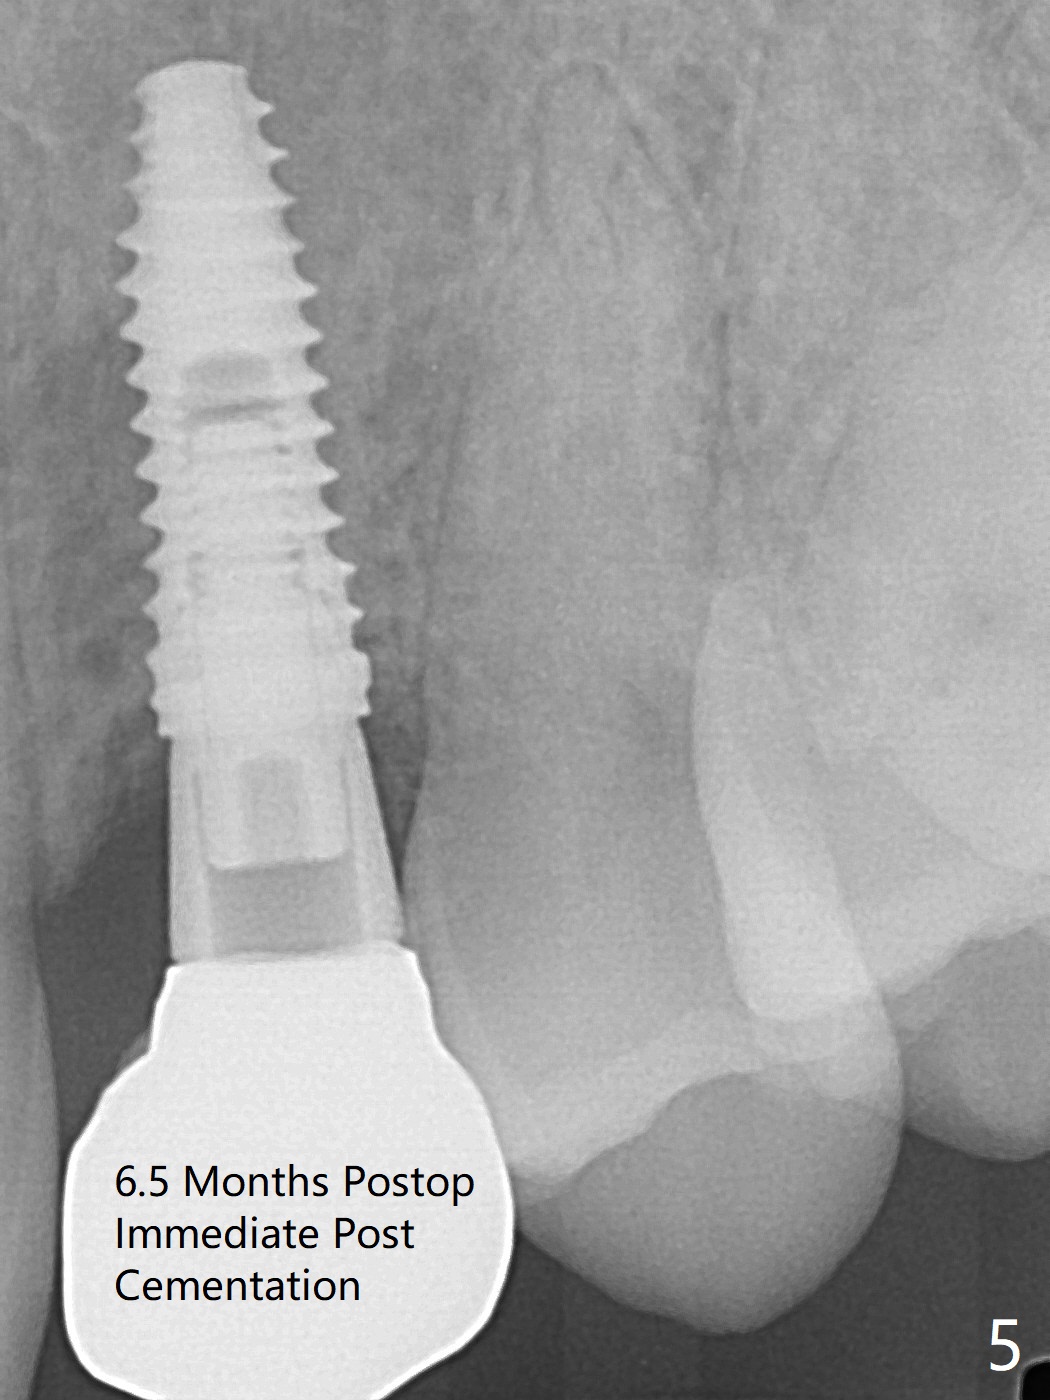

When the guide with 10.5 mm offset is seated at #11 after extraction, it looks buccal. Pointed drill creates an entry point in the mesial portion of the socket. PA, taken following 2.2x11.5 mm drill, shows acceptable mesiodistal trajectory (Fig.1). When a 3.5x11.5 mm implant is placed, it is difficult to withdraw the driver from the metal tube (Fig.1 *). There is no buccal gap with plenty of the lingual gap. A 4x3 mm x15 degree A-type angled abutment is placed (Fig.2). It appears that the dense palatal plate deviates the osteotomy and implant placement (as compared to the design, Fig.3). In fact osteotomy should have been prepared until 4 mm in diameter before increase in depth with 2.2 and 3 mm drills to eliminate buccal deviation. The ideal drill sequence would be point drill, 2.2x8.5 mm drill, 3x8.5, 3.5x8.5, 2.2x10, 2.2x11.5, PA to confirm trajectory, 3x10, 3x11.5 and 3x13. Torque associated with implant placement is pure, not derived from friction between the driver and the metal tube. There is mesial crestal bone loss 4 months postop (Fig.4, as compared to immediate postop in Fig.2 (*)). Crestal bone loss does not get worse between 4 and 6.5 months postop (Fig.4,5). The bone density increases 8 months post cementation (Fig.6).